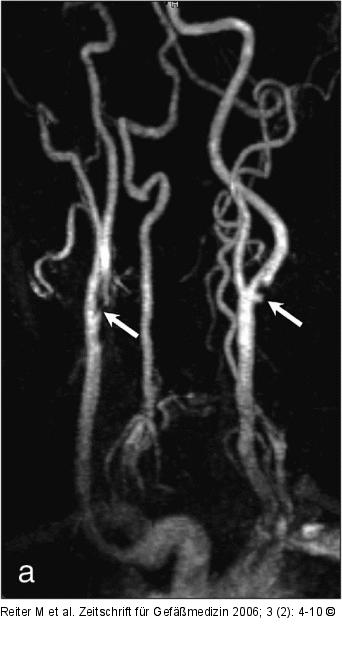

Abbildung 4a-b: Arteria carotis interna (a) MR-Angiographie der Karotiden. Bds. findet sich eine Stenose der A. carotis interna: rechts eine Fadenstenose, links eine ~70%-Stenose mit verifiziertem Ulkus. (b) zeigt die korrespondierende i. a. DSA-Aufnahme der linken Seite; (Z) zeigt die ACI-Stenose. |

(a) MR-Angiographie der Karotiden. Bds. findet sich eine Stenose der A. carotis interna: rechts eine Fadenstenose, links eine ~70%-Stenose mit verifiziertem Ulkus. (b) zeigt die korrespondierende i. a. DSA-Aufnahme der linken Seite; (Z) zeigt die ACI-Stenose. |